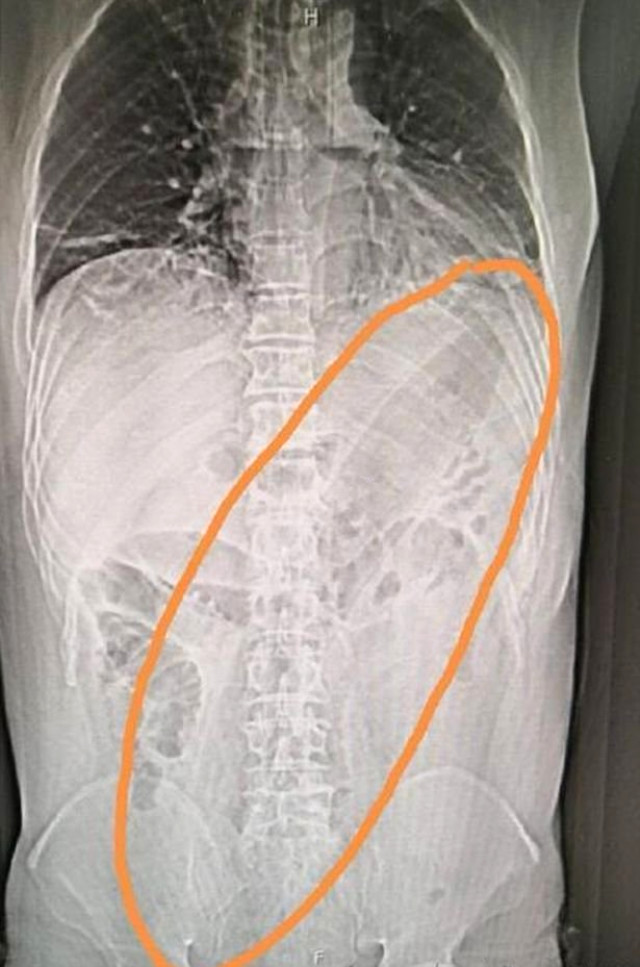

Çin, son yılların en şaşırtıcı tıbbi olayını konuşuyor. Çin'de ismi açıklanmayan hasta geçtiğimiz hafta mide bulantısı ve karın ağrısı şikayetiyle hastaneye gitti. Röntgeni çekilen adamın anüsünden 30 santimetrelik patlıcan çıktı.

Yapılan incelemeler ve röntgen sonuçlarına bakarak adama soru soran doktorlar aldıkları yanıtla iyice şaşkına döndü. Acı içinde kıvranan adam sindirim ve boşaltım sorununu ortaya kaldırmak için anüsünden 30 santimetre uzunluğundaki bir patlıcan soktuğunu ve bunun 2 gündür içinde sıkıştığını söyledi. Şok içindeki doktorlar adama derhal müdahale ederken yapılan operasyon sonrasında adamın sağlık durumunun düzeldiğini açıkladı.

Patlıcan aracılığıyla kolonu genişletmeye çalıştığını söyleyen adamın, bu tedavi yöntemini büyüklerinden öğrendiğini söyledi.